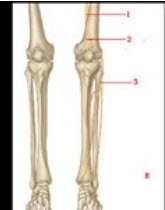

看图做题:

第1题,共1个问题

(配伍题)

如图B中1所示为下肢哪根神经( )

如图B中2所示为下肢哪根神经( )

如图B中3所示为下肢哪根神经( )